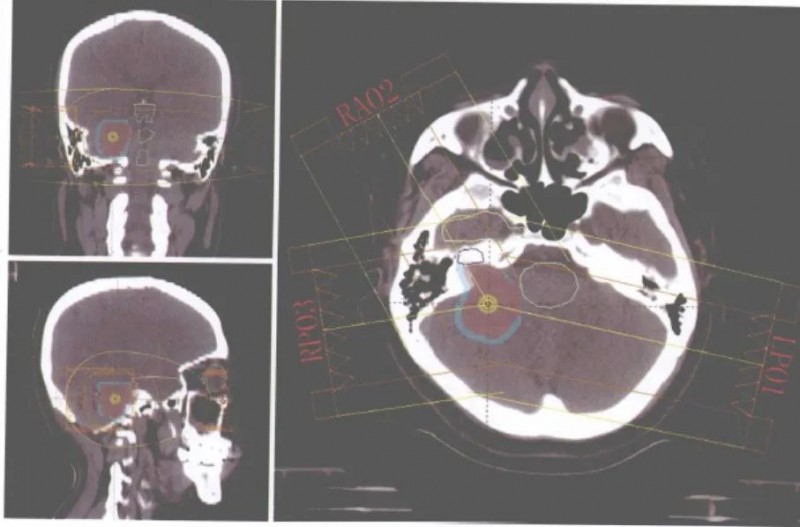

听神经瘤用质子刀做好吗,质子治疗听神经瘤病例参考听神经瘤治疗听神经瘤的发病率为0.1/10万。听神经瘤生长较慢,大多仅生长在一侧,其主要症状是进行性听力下降,或伴有耳鸣和眩晕,并有6%的可能突然出现失聪。保持听力和不损害面神经是治疗听神经瘤的关键。目前,外科手术仍是首选的治疗方法。然而,许多患者不适合外科手术,或手术后肿瘤复发,放射外科便成为更好选择的治疗方

质子重离子治疗听神经瘤,听神经瘤用质子刀做好吗,来看看这个案例 头颈癌

质子重离子治疗听神经瘤,听神经瘤用质子刀做好吗,来看看这个案例退休在家的张叔在2009年出现右耳耳鸣伴听力下降,逐渐加重至右耳完全失聪。2011年7月行颅脑MR检查,发现右侧CPA区软组织信号影,轴位最大面积约2.2*1.4cm,考虑右侧听神经瘤。2012年4月颅脑MR示病灶增大到2.5*1.5cm,脑干受压。因为病灶未明显影响到生活质量,略有些固执的张叔不